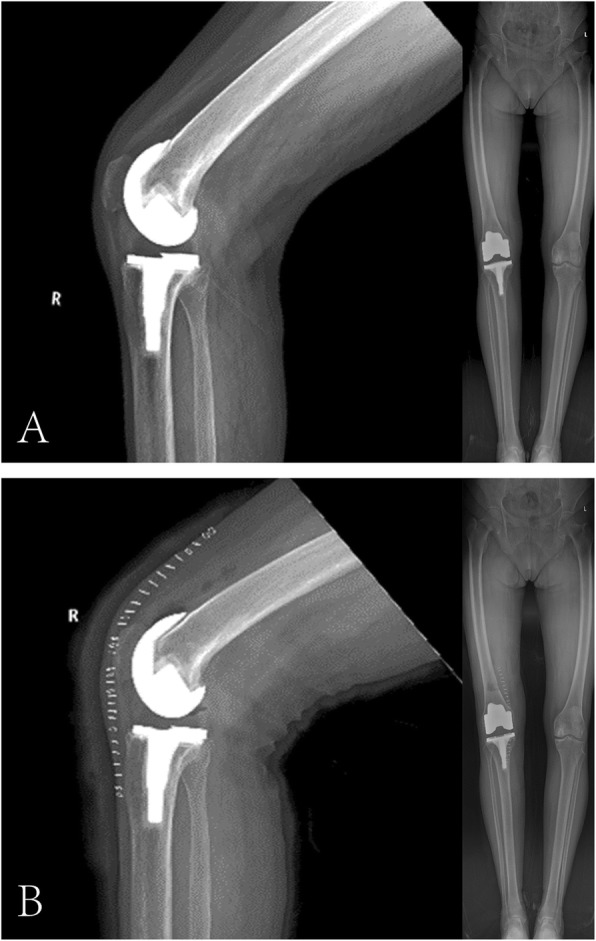

Plain radiographs demonstrated that the prosthesis was well-placed and well-fixed without any signs of periprosthetic fracture, implant loosening or osteolysis (Fig. 2a). Magnetic resonance imaging (MRI) was not performed. A diagnosis of arthrofibrosis after TKA was established and neuroma was also highly suspected due to the positive result of Tinel’s sign.

Fig. 2.

a Pre-revision standing anterior lateral radiograph of the right knee joint, revealing that the prosthesis was well-placed and well-fixed. b Post-revision radiograph of the right knee joint

The patient resumed knee exercise 2 days after surgery and recovered uneventfully. She had complete resolution of right knee pain without pain medication (VAS 2/10 on 2nd postoperative day, VAS 0/10 at 2 weeks postoperatively). The ROM of the right knee was 0° to 110° on the 2nd postoperative day (Fig. 1c and d) and increased to 0° to 120° at 2 weeks postoperatively. The post-revision radiograph revealed similar fixation and placement as pre-revision (Fig. 2b). The pathological report showed that the specimen contained fat, blood vessels, collagen and nerve tissue, and the arrangement of nerve fiber bundles were haphazard, which was considered to be a traumatic neuroma (Fig. 4).